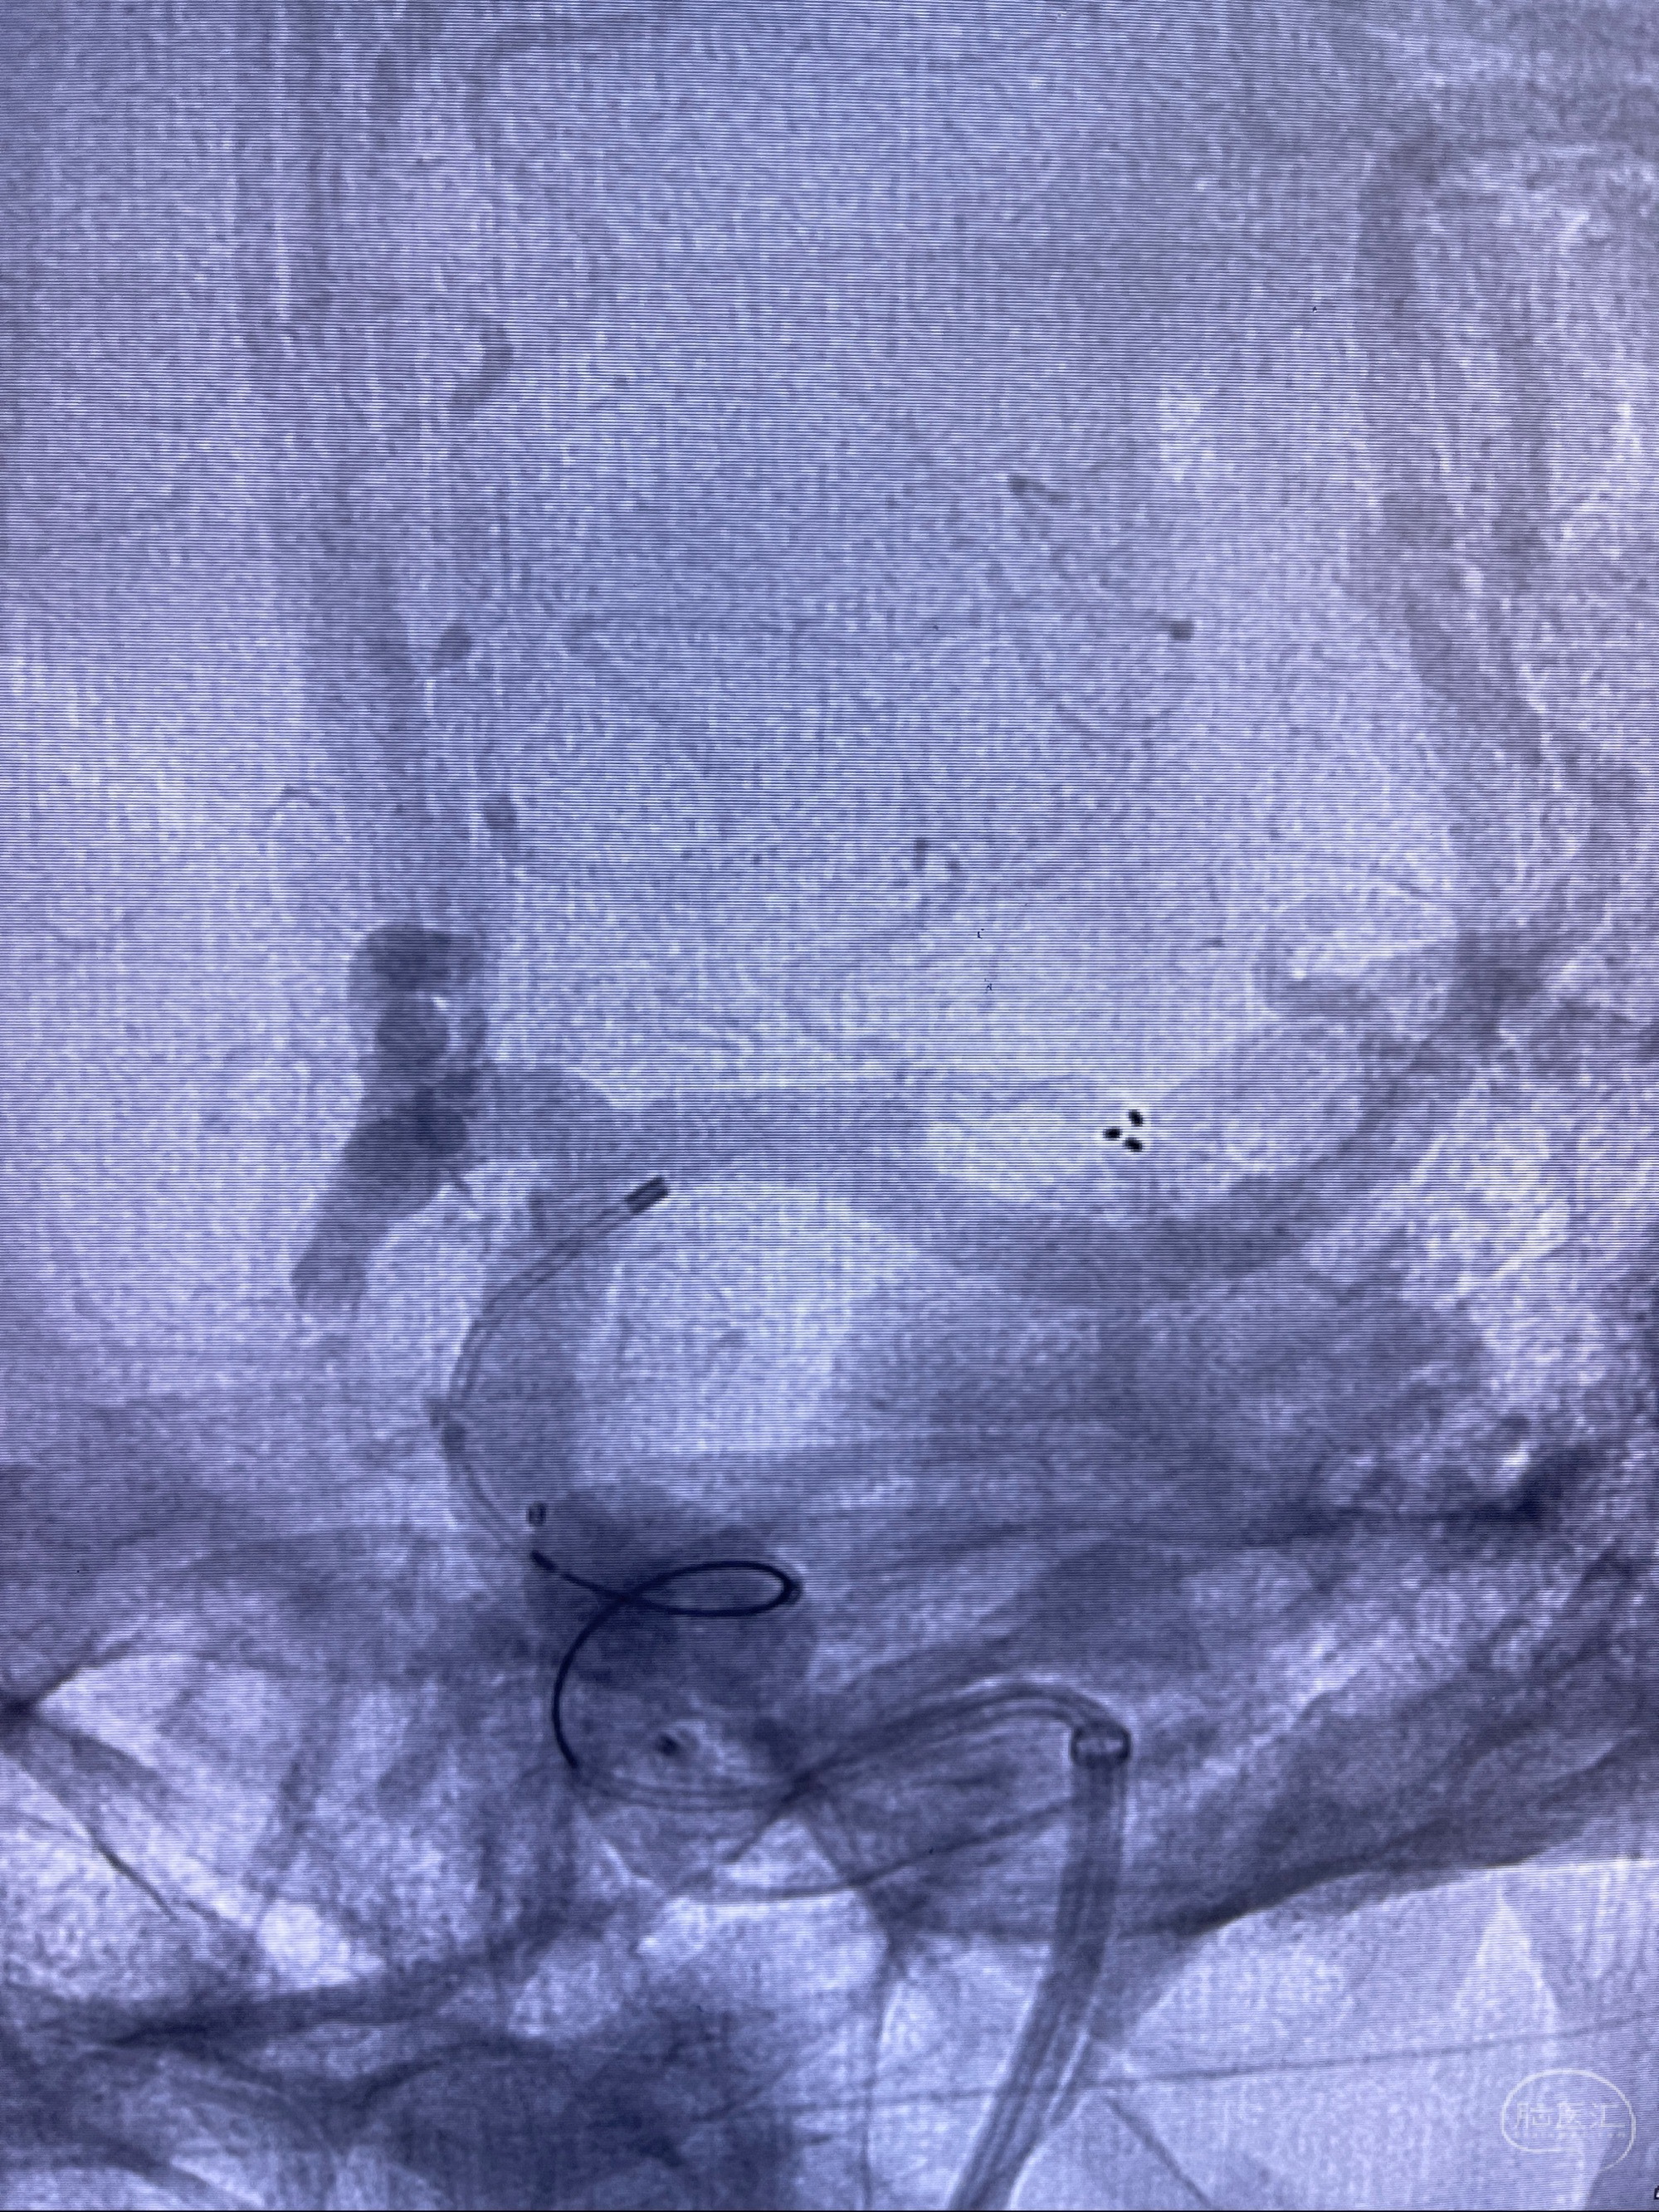

2023-08-14DSA:

左侧大脑中动脉动脉瘤,约2.6-2.8-3.4-2mm大小(瘤颈部、瘤体部、瘤高)

1.左侧大脑中动脉动脉瘤,约2.6-2.8-3.4-2mm大小(瘤颈部、瘤体部、瘤高)

2.外科手术夹闭or介入支架辅助栓塞